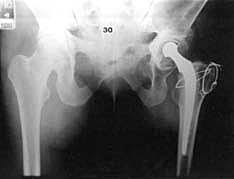

• Primer artroplastia total de cadera

Primer artroplastia total de cadera

Se realiza en este año el primer reemplazo total de cadera.

• Creacion de Endoprotesis bipolares usadas hasta la actualidad.

Creacion de Endoprotesis bipolares usadas hasta la actualidad.

Giliberti y Bateman, desarrollaron los prototipos de las actuales endoprótesis bipolares, empleando copas metálicas revestidas con polietileno de alta densidad y cerradas sobre la cabeza femoral.